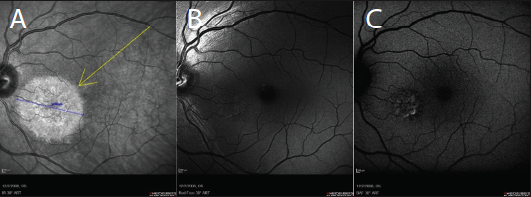

Figure 3. cSLO imaging modalities: infrared (A), red-free (B), and BluePeak autofluorescence (C).

The device’s confocal scanning laser ophthalmoscope (cSLO) technology allows operators to steer the OCT to image pathology in the far retinal periphery. It can also be used to noninvasively scan patients through pupils as small as 1 mm and with no light-off restrictions. Furthermore, multicolor, red-free, FA, and FA plus indocyanine green (ICG) imaging (Figure 3) can be initiated with pupils at 2 mm, thus reducing wait times for patients to dilate.